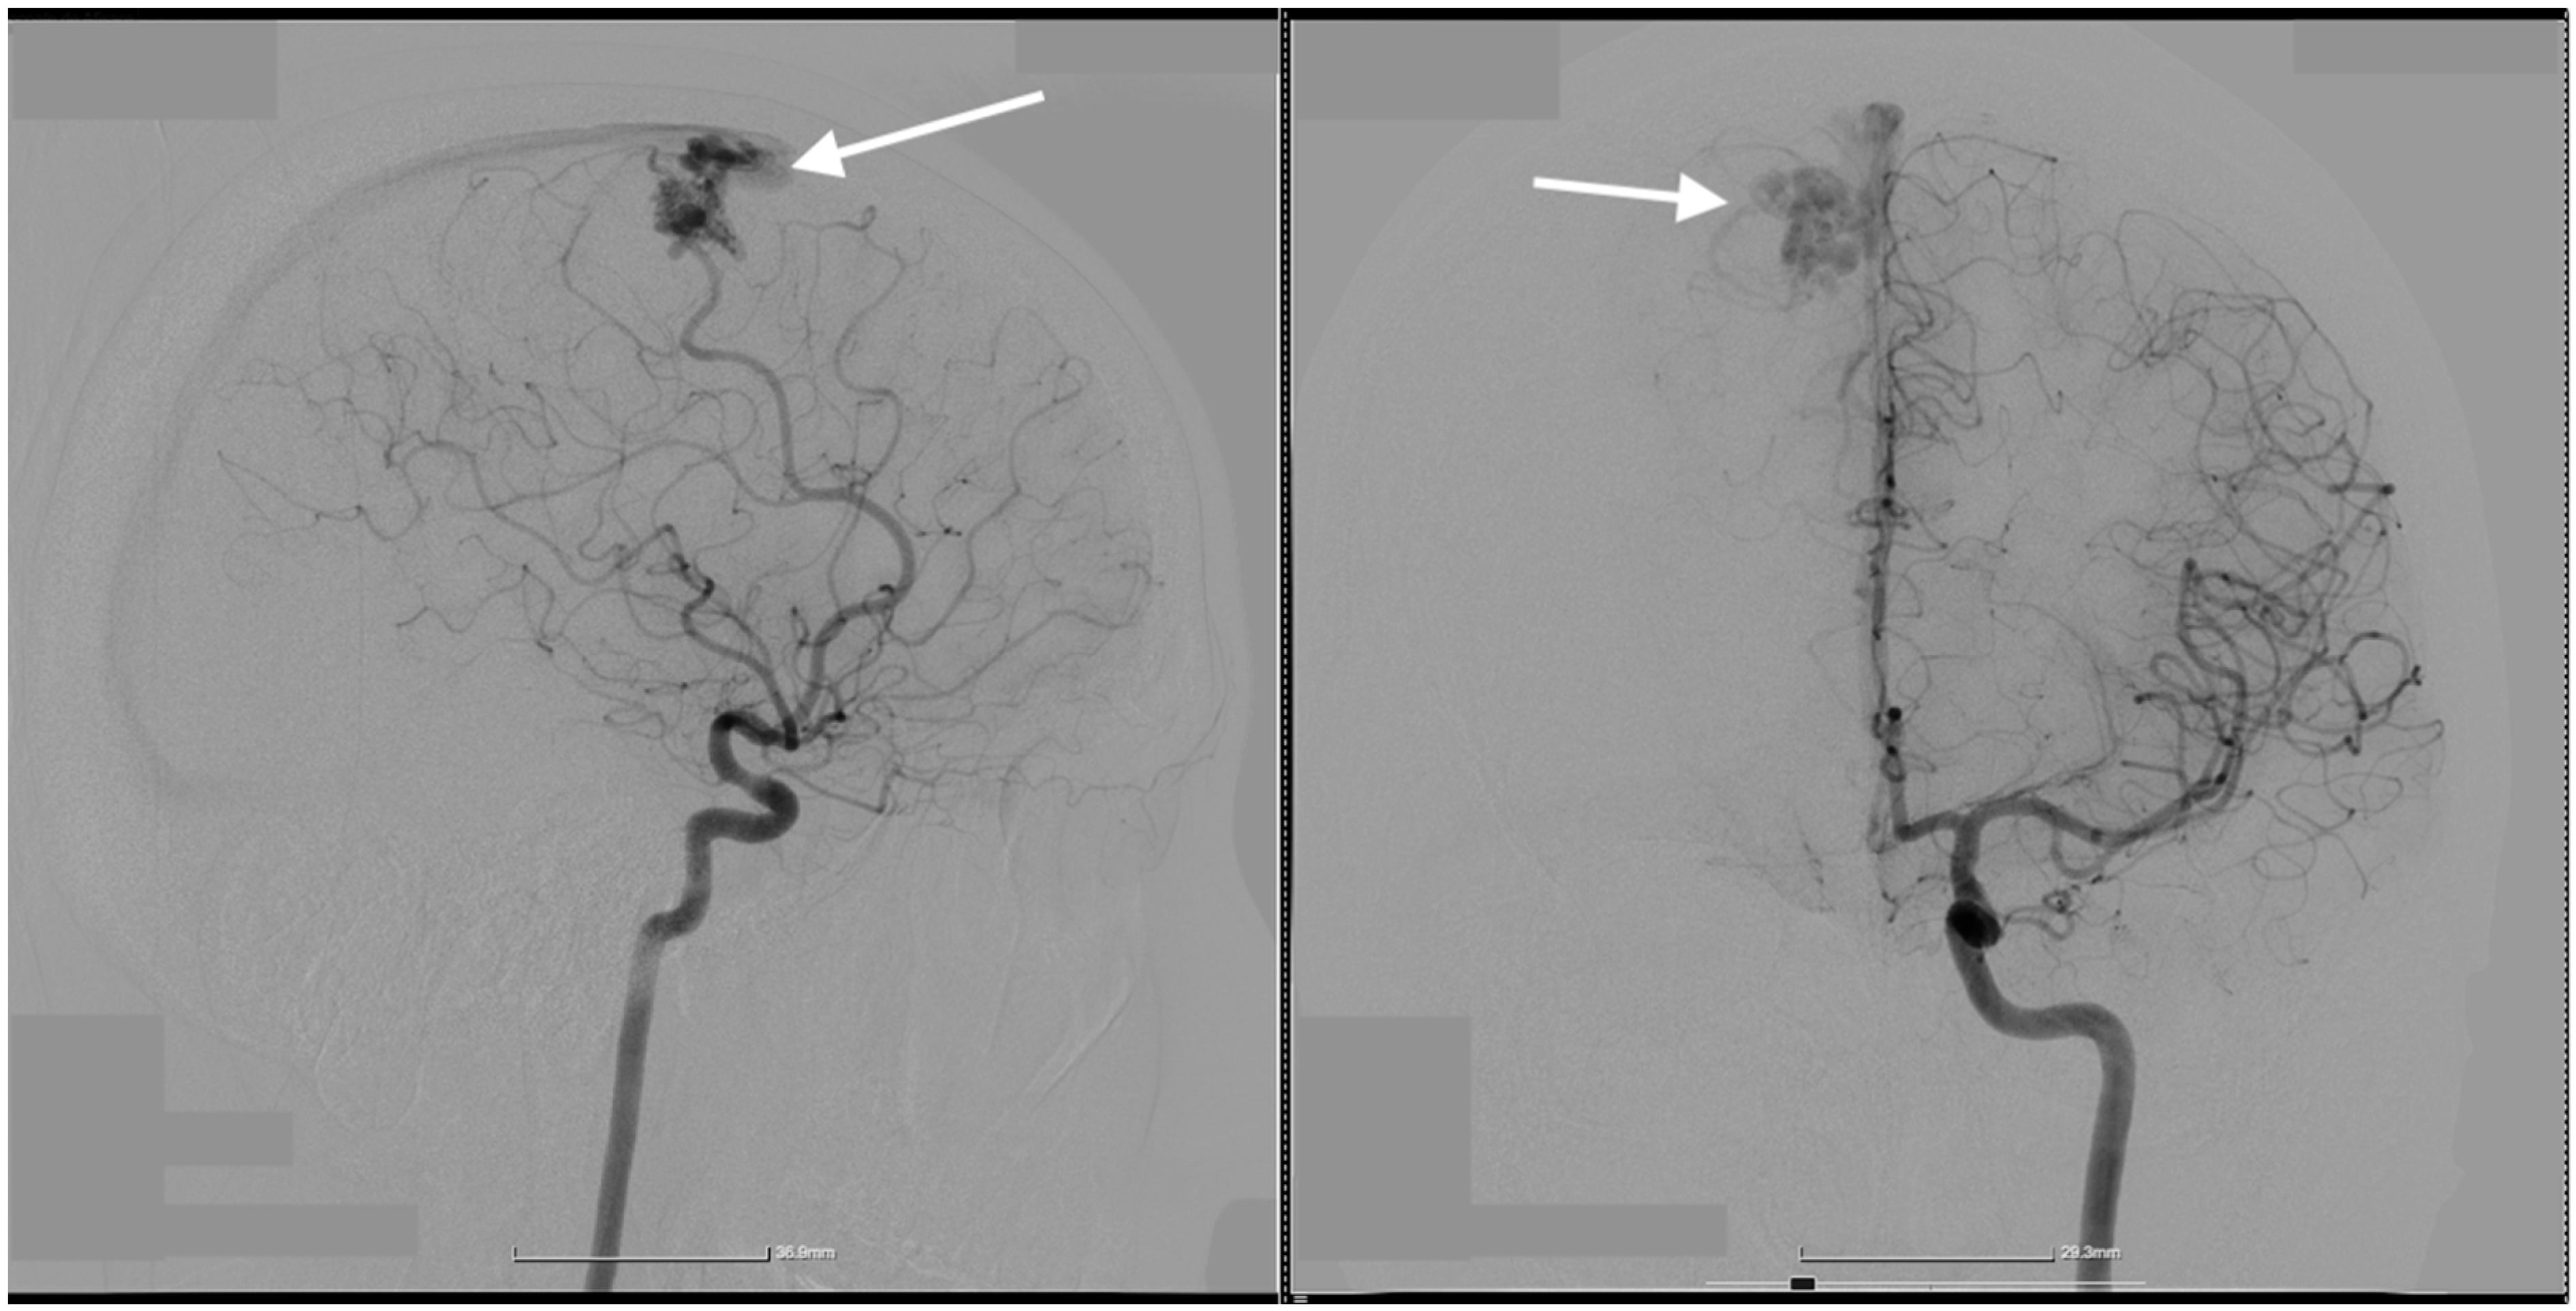

2. Case Presentation